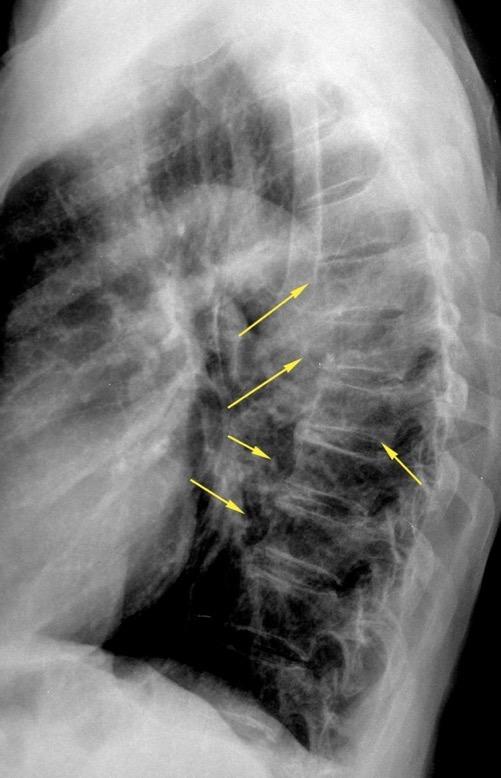

Líneas paraespinales formando un “paréntesis” por encima del diafragma. El signo señala el origen “intratorácico” de la lesión.

Conrad A et al. Pott’s disease associated with large and multiple abscesses in a 30-year-old migrant from Chad. BMJ Case Rep 2018

(lesiones toracoabdominales) La divergencia de las líneas paraespinales apunta a lesión toracoabdominal, que desde el tórax desciende y penetra en el abdomen.

Signo del “iceberg” positivo en Tb vertebral

Afectación por vía hematógena. Región dorsolumbar más frecuente. Afectación inicial: irregularidad de los platillos vertebrales, disminución del disco intervertebral con esclerosis ósea adyacente. Kim. Radiographics.2001